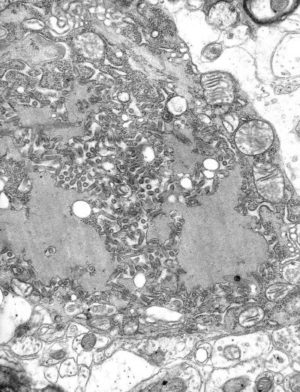

狂犬病ウイルスの電子顕微鏡写真(灰色の円形から棒状の粒子)wikipediaより

狂犬病とは、「狂犬病ウイルス」という病原体によって引き起こされ、人も動物も発病するとほぼ100%死亡するという恐ろしい感染症です。